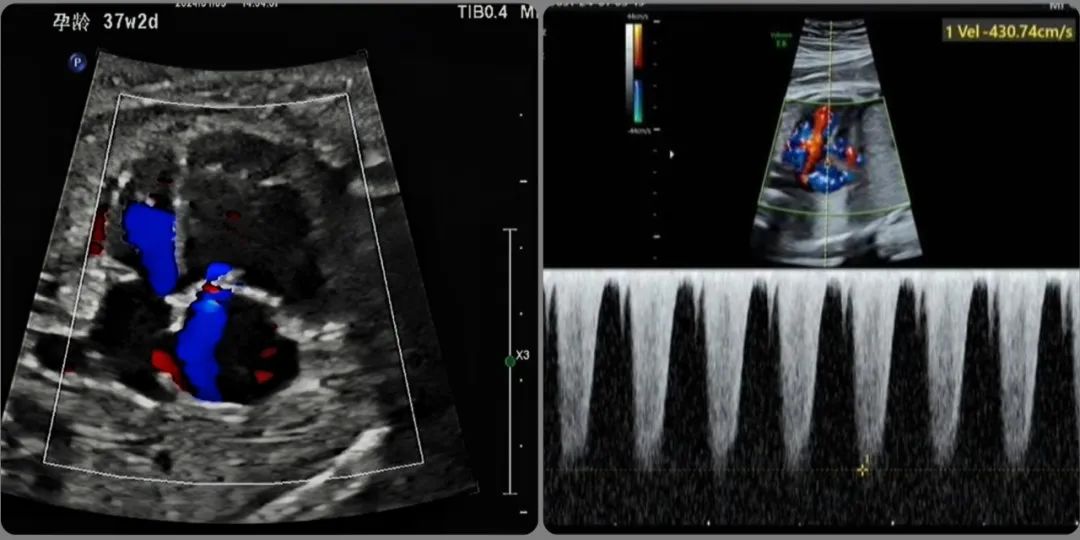

近日,锦州市妇婴医院(妇幼保健院)超声科高医生在给一位孕37周+2天的准妈妈常规超声检查中,意外发现胎儿右心增大伴三尖瓣大量反流,这让她警惕起来。

经邵雪竹和李雯睿两位主任的会诊,发现胎儿除了右心扩大,三尖瓣重度反流外,还存在肺动脉扩张,肺动脉瓣反流,动脉导管走行迂曲,血流加快,局部狭窄,内径1mm,动脉导管少量反流,估测肺动脉压力>60mmHg,静脉导管a波反向,考虑胎儿动脉导管狭窄,即将关闭,并出现右心衰。